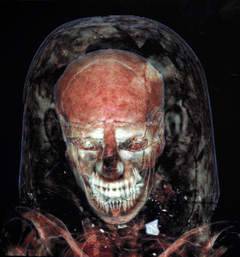

La vita torbida dei tempi della collezione antica Field delle mummie, la più grande delle Americhe, recentemente si è un po' rischiarata. Dal 6 luglio, delle mummie selezionare dall'antico Egitto e Perù sono state fatte scansioni CT in un rimorchio, nel parcheggio del Museo. La macchina CT è stata donata da Genesi Medical Imaging in Huntley suburbana lontano a nord-ovest.

Le bare non possono essere aperto senza danneggiarle e radiografie standard erano piatte, distorto e in grado di catturare gli oggetti sotto altri oggetti. A Tac, in tre dimensioni, permette ai ricercatori un impareggiabile guardare ciò che si trova all'interno le bare ornate, come ad esempio il cedro 3.000 anni uno sdraiato sul letto TAC lunedì.

Le scansioni CT hanno contribuito a determinare il sesso, l'età e la causa della morte delle mummie. Hanno anche fornito dettagli sulle tecniche di mummificazione e sepoltura oggetti, ad esempio una figurina di dea e pentola piccola offerta trovato all'interno della bara della mummia peruviana, Brown ha detto.